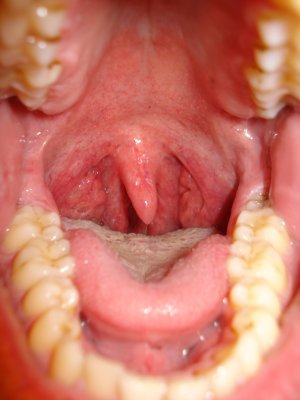

вот пара снимком от 2006 года и пара снимков сегодняшних... надоело оно мне (горло) вот и пишу, может есть решение проблемы.....

так вот, лет с 10-15 назад хорошенько простыл, болело горло и т.д. (стандартные симптомы), но после этого постепенно стали появляться язвы на миндалинах, которые всё это время только прогрессировали и сейчас, когда простываю, они начинают как бы гнить и обростают (наверно) гнойниками (достаточно твёрдые на ощупь, если достать от туда) и пахнут крайне зловонно, когда вроде здоров гнойники исчезают, НО остаются уже сквозные дырки в которые забивается пища и тоже гниёт и пахнет! когда сильно это надоедает начинаю чистку, просто беру тонкую палочку с ваткой и каждую дырку в миндалинах прочищаю, весь мусор из дырок удаляю и после этого миндалины вроде как даже здоровее становятся и запах пропадает!

вопрос специалистам вот в чём: как эти дырки заживить, чтобы в них заново не образовывались гнойники и чтобы в них не попадала пища?